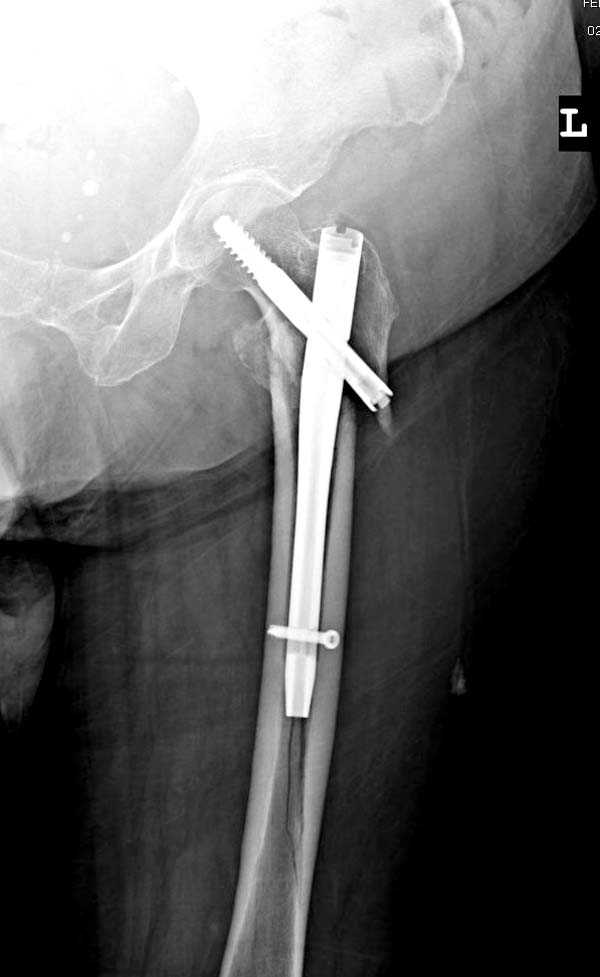

Здесь представлен случай, где в послеоперационном периоде обнаружена техническая ошибка, Gamma 3 установлен с нарушением методики. Больная в 91 лет, прооперирована через день после поступления и выписана через 48 часов.

При первом послеоперационном поликлиническом осмотре больная предъявила жалобы на боли в бедре. В серийных снимках обнаружен продольный перелом верхнего отдела бедра.

Считаем, что техническая ошибка произошла во время установки гвоздя, когда рассверливанию канала не уделили должного внимания. Канал остался узковат, и гвоздь был забит с силой. Полная нагрузка конечности приостановлена на две недели, и боли в конечности изчезли. Больная начала нагрузку и перелом срастается.-- Djoldas Kuldjanov, M.D.Associate ProfessorDepartment of Orthopedic SurgerySt. Louis University